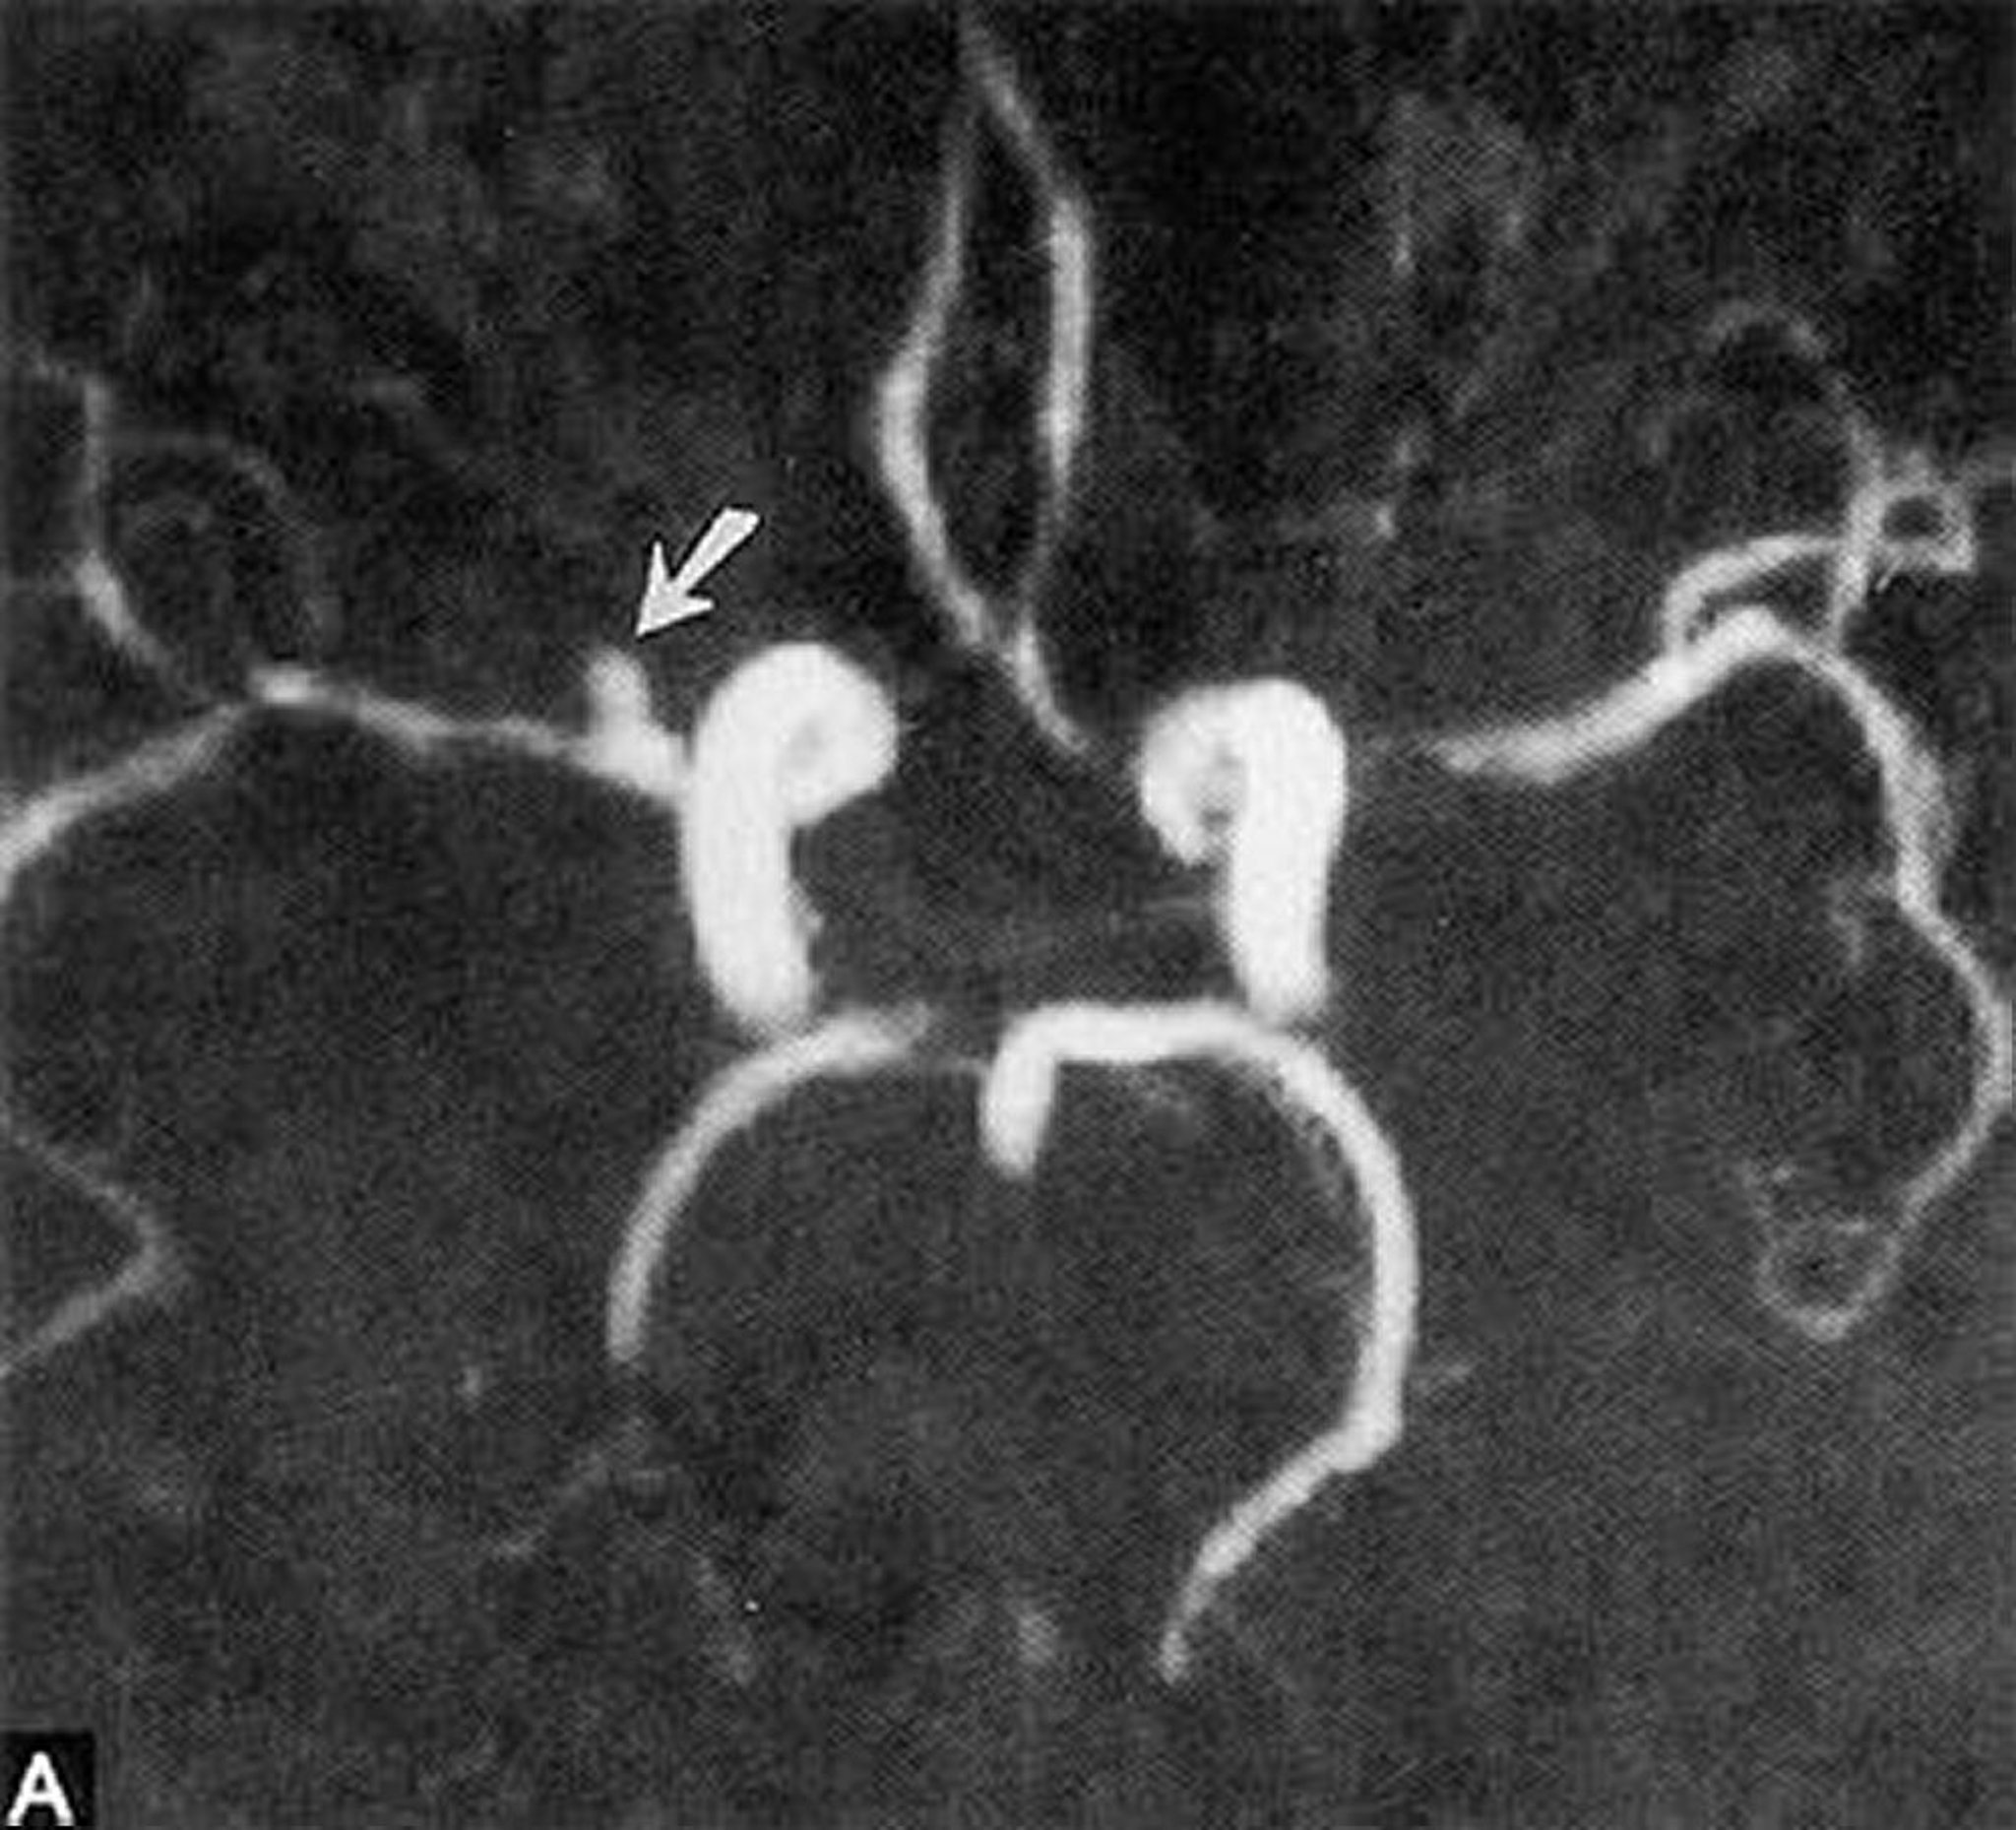

This magnetic resonance angiogram shows a small saccular aneurysm of the horizontal right middle cerebral artery (arrow).

By permission of the publisher. From Ritter A, Hayman L, Charletta D. In Atlas of Cerebrovascular Disease. Edited by PB Gorelick and MA Sloan. Philadelphia, Current Medicine, 1996.